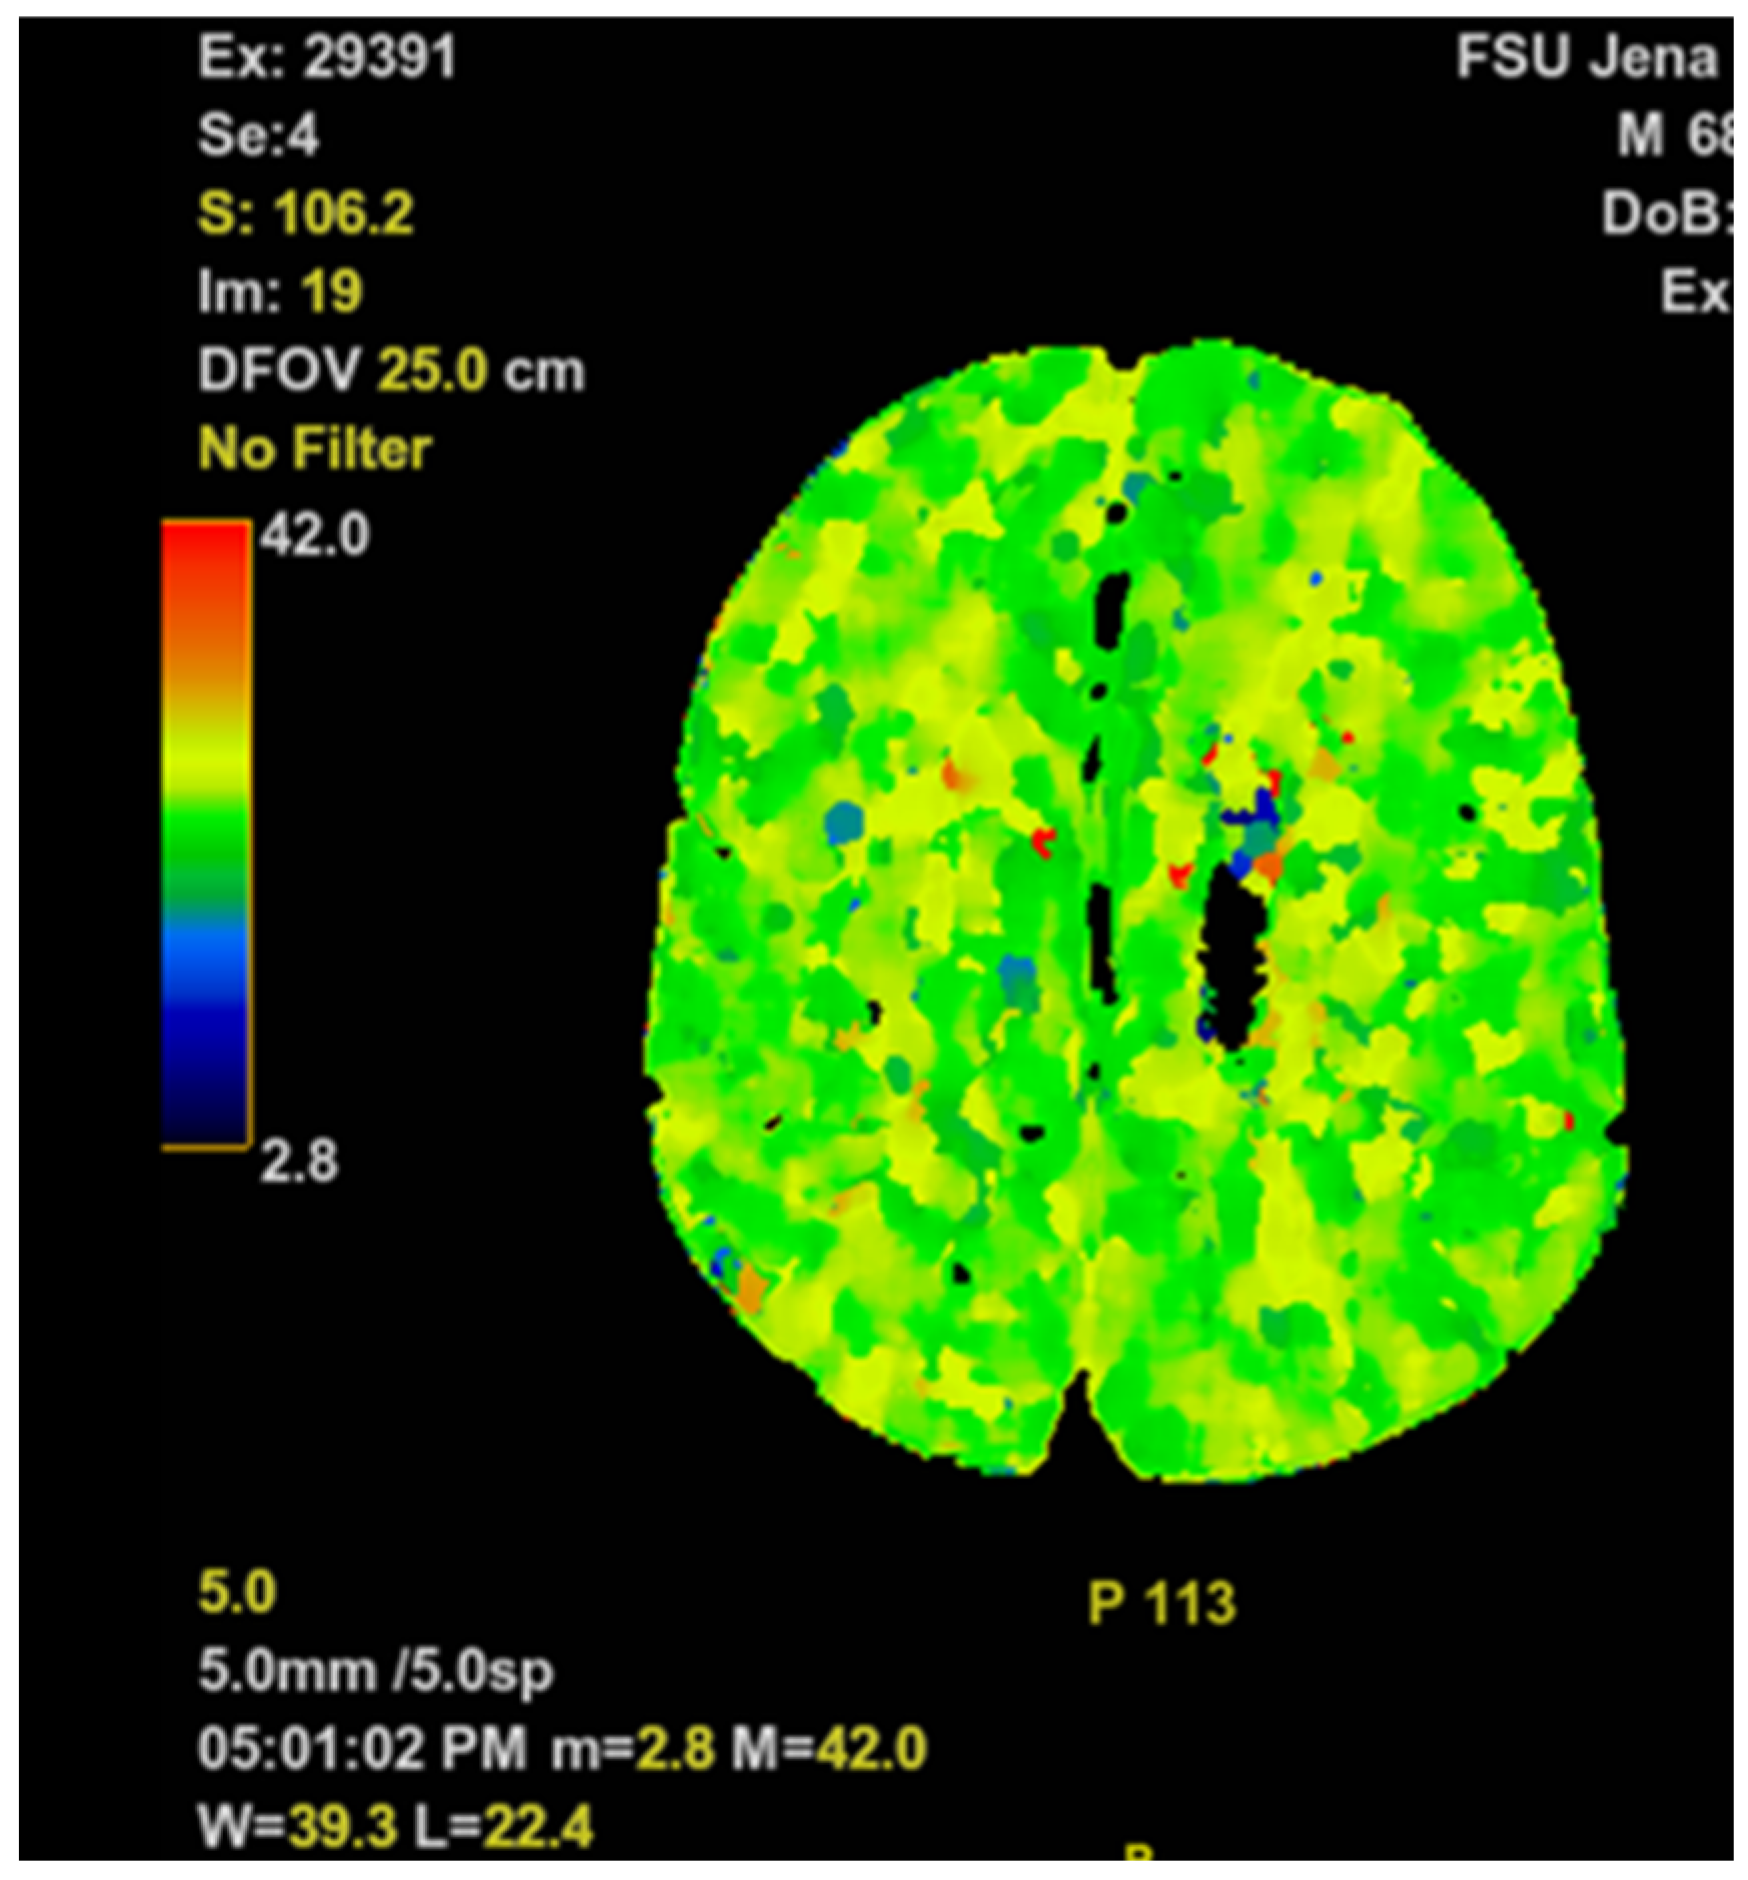

No specific treatment was initiated at the inpatient dermatology, since shortly after admission he developed severe tachydyspnea and a generalized tonic-clonic seizure, followed by a prolonged postictal state with impaired consciousness (Glasgow Coma Scale [GCS] of 5 points). An episode of supraventricular tachycardia with a heart rate of 100 beats per minute was observed, while blood pressure remained within normal limits. On high-flow nasal cannula with 15 liters per minute, his peripheral oxygen saturation did not exceed 88%. Endotracheal intubation was performed by the hospital emergency team without complications. Head and chest CT scans were obtained (see Figure 1 and Figure 2).

There was no history of congestive heart failure, arrhythmias or coronary artery disease. The patient’s wife denied recent episodes of chest pain, palpitations, fatigue or edema. All chest imaging studies came back normal, without any signs of pneumonia or other significant pulmonary diseases (see Figure 2). The head CT scan showed no sign of an acute cerebrovascular event (see Figure 1). The standard ECG and CMP could not explain his symptoms. C-reactive protein (CRP) (8.9 (< 5) mg/L) and white blood cell count (WBC) (11.6 (4.4–11.3) gpt/L) were slightly increased on admission to the ICU, while procalcitonin (0.08 (< 0.5) ng/L) remained unremarkable. Urinalysis revealed leukocyturia, consistent with the mildly elevated CRP and WBC. PCR testing for SARS-CoV-2 was negative. No fever was detectable, and the differential white blood count analysis was within normal limits. Mild anemia was observed (hemoglobin (Hb) 6.9 (8.7–10.9) mmol/L).

Figure 1. Representative cerebral perfusion scan slice of the head imaging study.